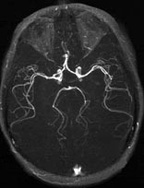

Magnetic Resonance Angiography (MRA), is a technique to demonstrate the vascular system without an injection of a material to make it show up, though an injection may be used to enhance the effect. The image to the left is an MRA of the brain, showing the cerebral arteries, and the vessels of the circle of Willis.

The image to the left is an MRA of the brain, showing the cerebral arteries and the vessels of the circle of Willis.